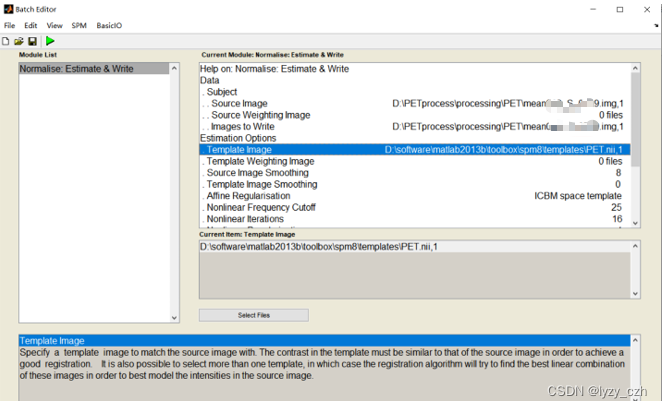

弹出以下窗口,只需编辑Source Image, Images to Write和Template Image;其他参数不动,最后点击左上角蓝色三角形运行